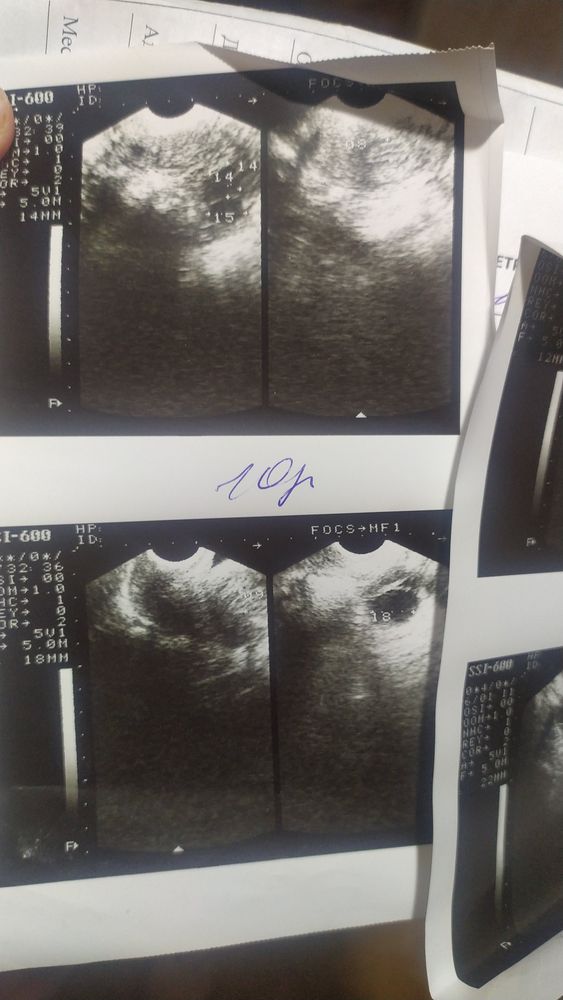

Всем привет. 5 августа было прерывание беременности ЗБ, чистка под наркозом. Сделали первое УЗИ и обнаружили повреждённые эндометрии. Вопрос у кого была схожая ситуация, что после чистки повреждённые эндометрии? долго восстанавливались и как? УЗИ прекреплю может кто поможет разобраться.

Врач говорит что если повреждённые эндометрии вдальнейщем могут плохо питать плаценту. Дело втором, что хочу как можно быстрее преступить к планированию беременности

На какой день цикла после М сделано узи? Сколько мм по заключению? На фото видать пробелы в эндометрии, но фото у вас не четкие. Я очень долго восстанавливала свой эндометрий после скаблежки((

Нина, чистка механическая была. При чистки повредили слой в матке. эндометрии теперь не равномерно расположены и появились места где эндометрии сильно поврежденны. Извиняюсь что не могу точно сказать как это называется

Что на картинках УЗИ вообще не понятно, яичники наверное.

Нина, есть разные слои эндометрия, если поврежден функциональный, то он может больше не нарастать в этих местах.

От сюда и такие "пробелы" на узи.